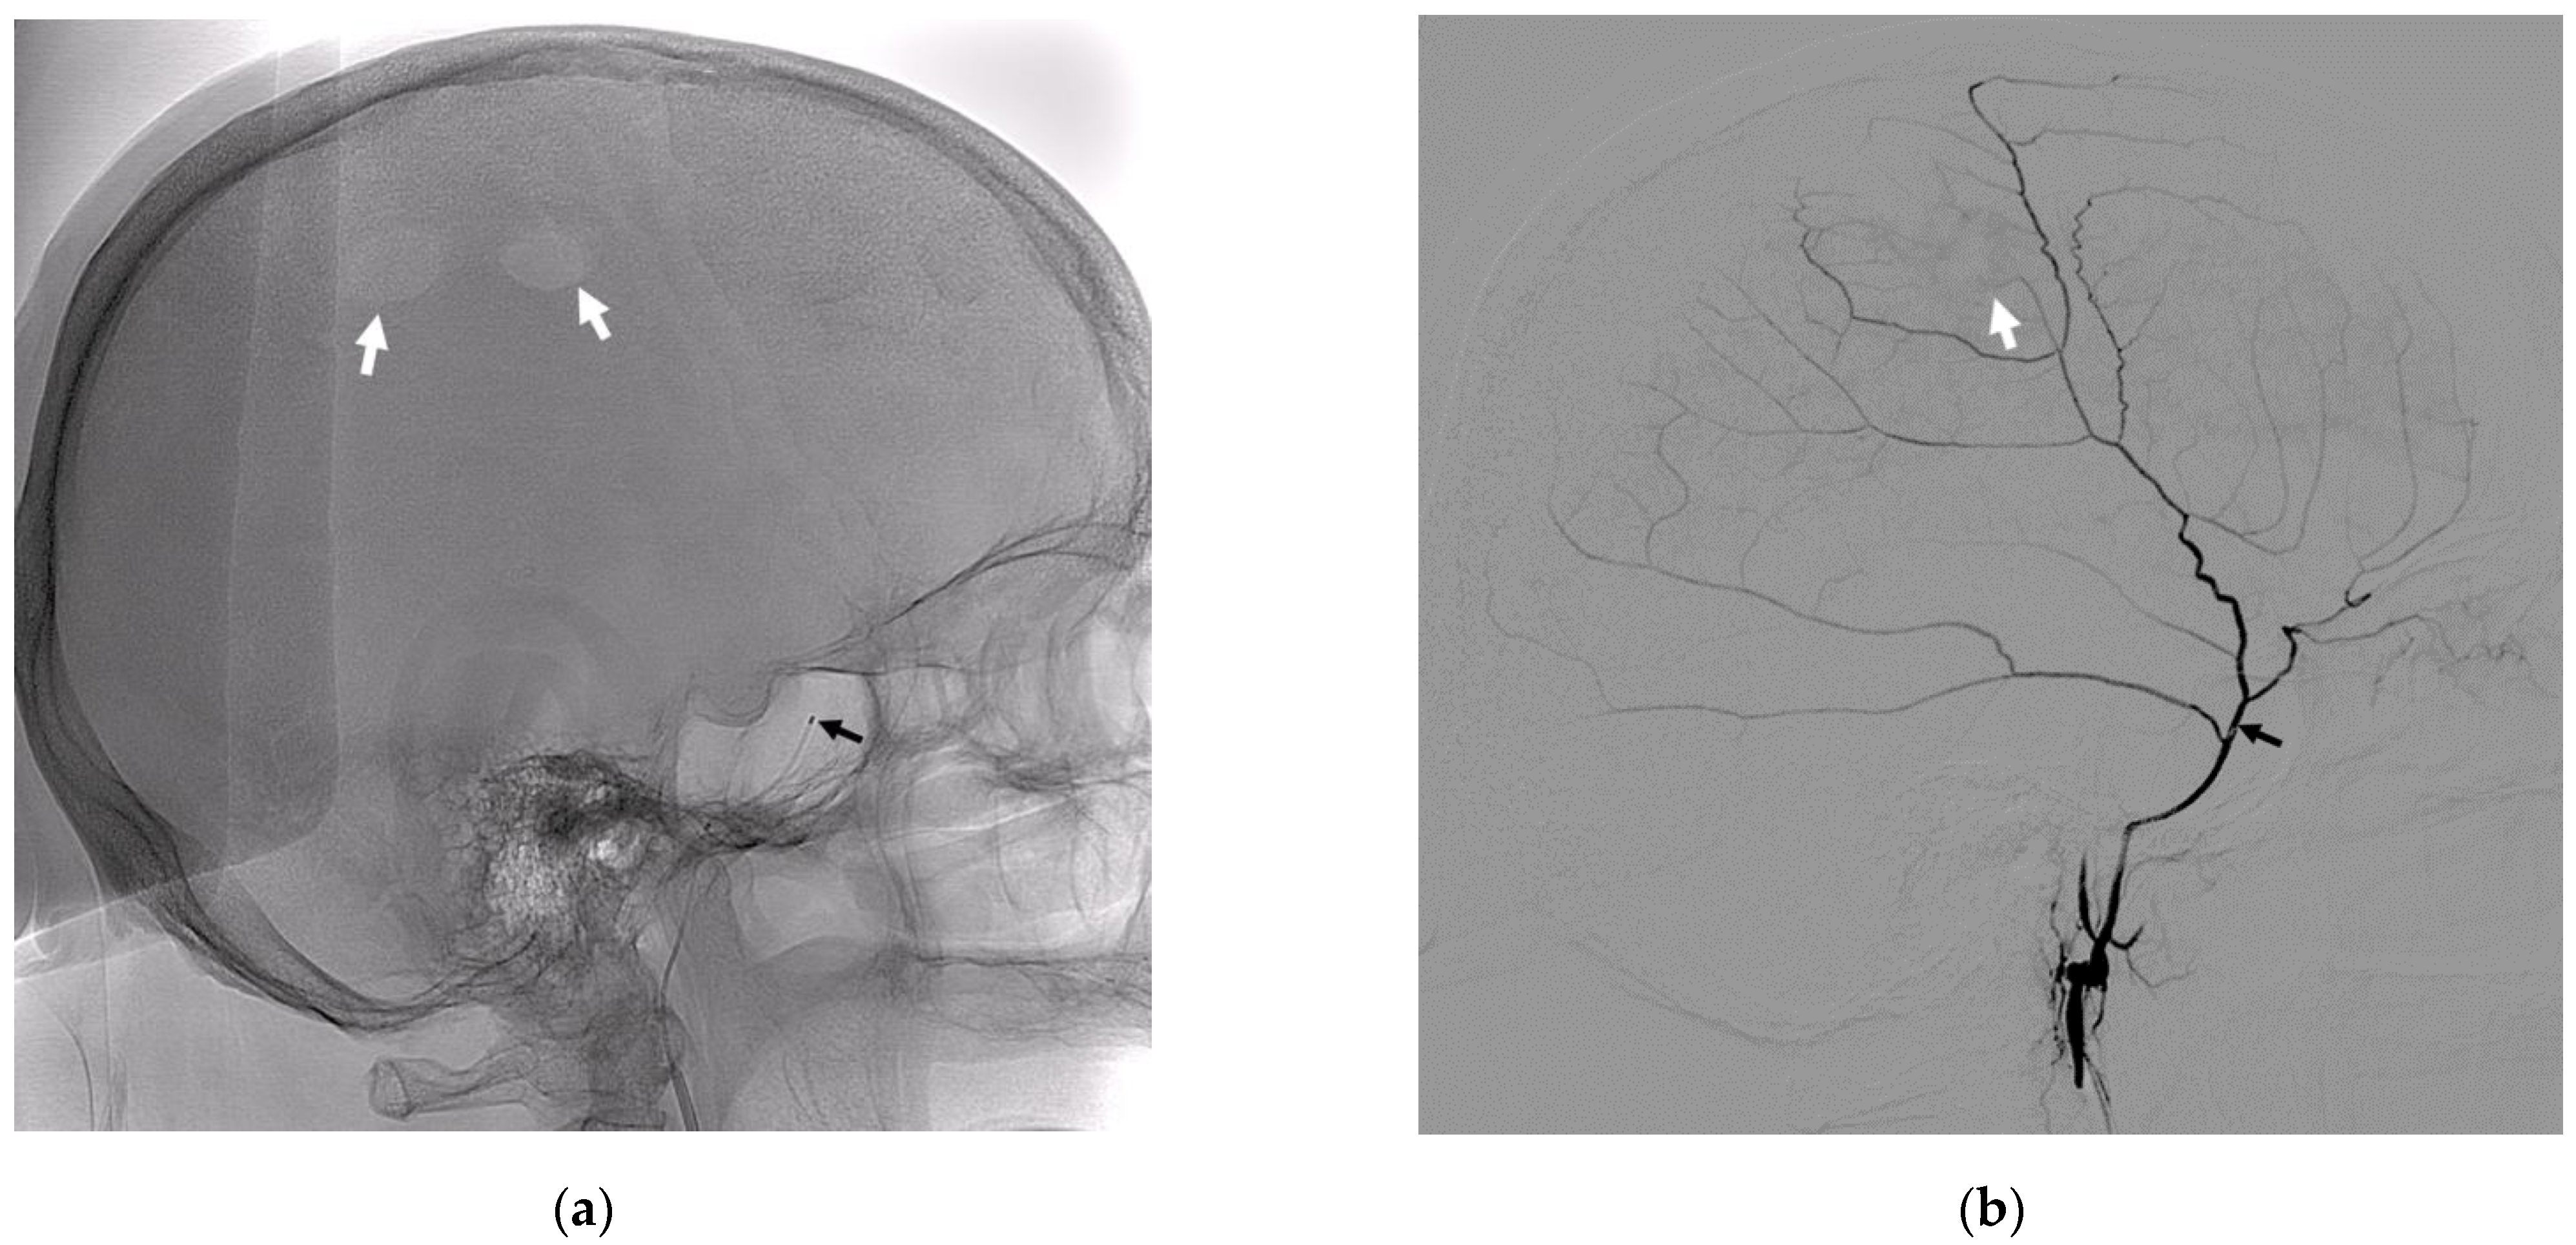

- Petrov, A.; Ivanov, A.; Rozhchenko, L.; Petrova, A.; Bhogal, P.; Cimpoca, A.; Henkes, H. Endovascular Treatment of Chronic Subdural Hematomas through Embolization: A Pilot Study with a Non-Adhesive Liquid Embolic Agent of Minimal Viscosity (Squid). J. Clin. Med. 2021, 10, 4436. [Google Scholar] [CrossRef] [PubMed]

- Petrov, A.E.; Rozhchenko, L.V.; Ivanov, A.A.; Bobinov, V.V.; Henkes, H. The First Experience of Endovascular Treatment of Chronic Subdural Hematomas with Non-Adhesive Embolization Materials of Various Viscosities: Squid 12 and 18. Voprosy Neirokhirurgii Imeni N.N. Burdenko 2021, 85, 80. [Google Scholar] [CrossRef]